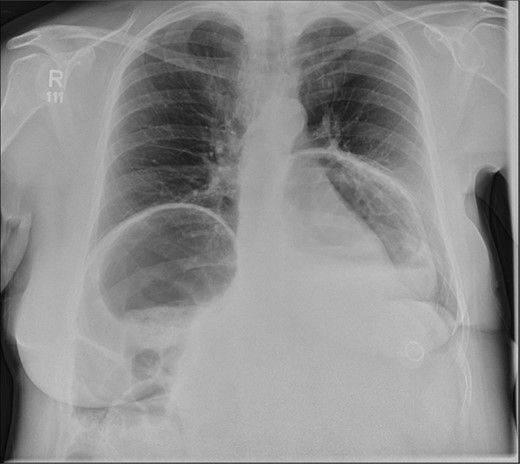

A 58-year-old female with a past medical history of a large intrathoracic hiatus hernia presented to her general practitioner and was subsequently referred to our surgical department with symptoms of sudden onset severe epigastric pain associated with vomiting and abdominal distension. Her abdomen was generally tender, maximally in the epigastric region, although she was not peritonitic. The admission erect chest radiograph showed a large hiatus hernia and an elevated right hemidiaphragm with a large loop of distended bowel (Fig. 1). Subsequent computed tomography (CT) scan demonstrated an almost completely intrathoracic stomach with a degree of volvulus, and the liver medially displaced by a loop of large bowel felt to be caecum (Fig. 2). Since the patient remained otherwise well, bidirectional endoscopy was performed, and given that a volvulus point could not be identified and the ileocaecal junction was not identified, contrast studies were requested (Figs 3–5) which demonstrated an incomplete obstruction caused by a volved caecum rotated anteriorly and cephalad.

Erect chest radiograph, showing a large hiatus hernia and large loop of bowel elevating the right hemidiaphragm.